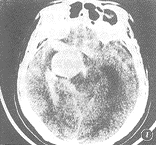

2.2.1 CT征象:平扫病灶呈圆形或类圆形稍高或高密度阴影,边缘较清晰。3例破裂动脉瘤周边可见环状高密度出血带伴脑室或脑池内积血(图1,2)。2例病变密度不甚均匀。1例见病灶周边有半环状钙化影。2例增强扫描病人病灶均明显强化,其中1例病灶均匀性强化,另1例可见瘤壁强化伴瘤体不甚均匀强化。

图1 右侧颈内动脉巨大动脉瘤伴破裂,CT示右侧鞍上池2.18 cm×2.85 cm之圆形高密度阴影,周围环以致密出血带